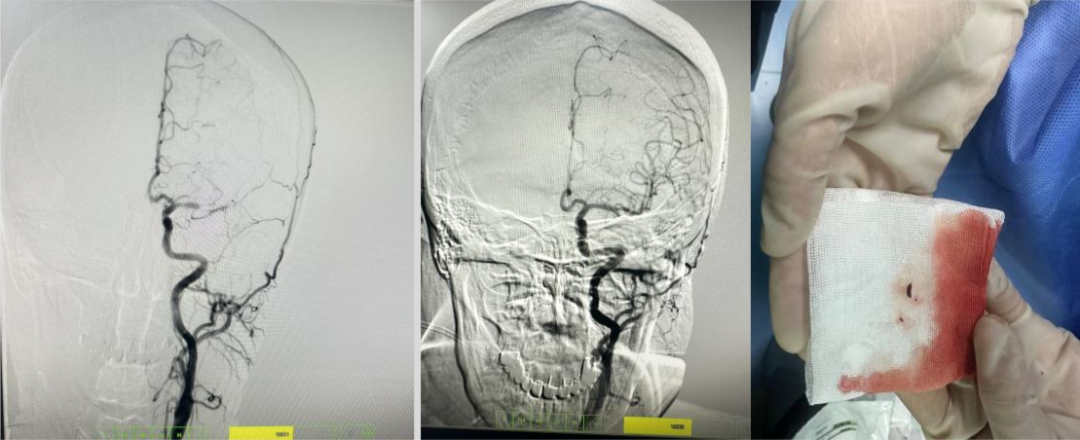

病历三:患者,78岁女性,因左侧肢体无力、右上肢抽搐、言语不清2小时伴意识模糊入院。

介入团队采取上述同样技术取出条块状暗红色血栓,质韧,考虑为心源性栓塞。

大脑中动脉M1段分叉部以远闭塞,大脑中动脉上干开通,取出血栓。

目前患者病情平稳,仍在治疗中。